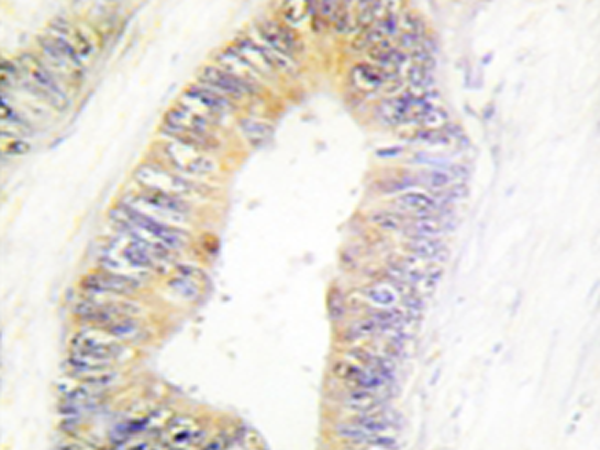

IHC positive control: |

Human colon carcinoma tissue |

IHC Recommend dilution: |

50-100 |